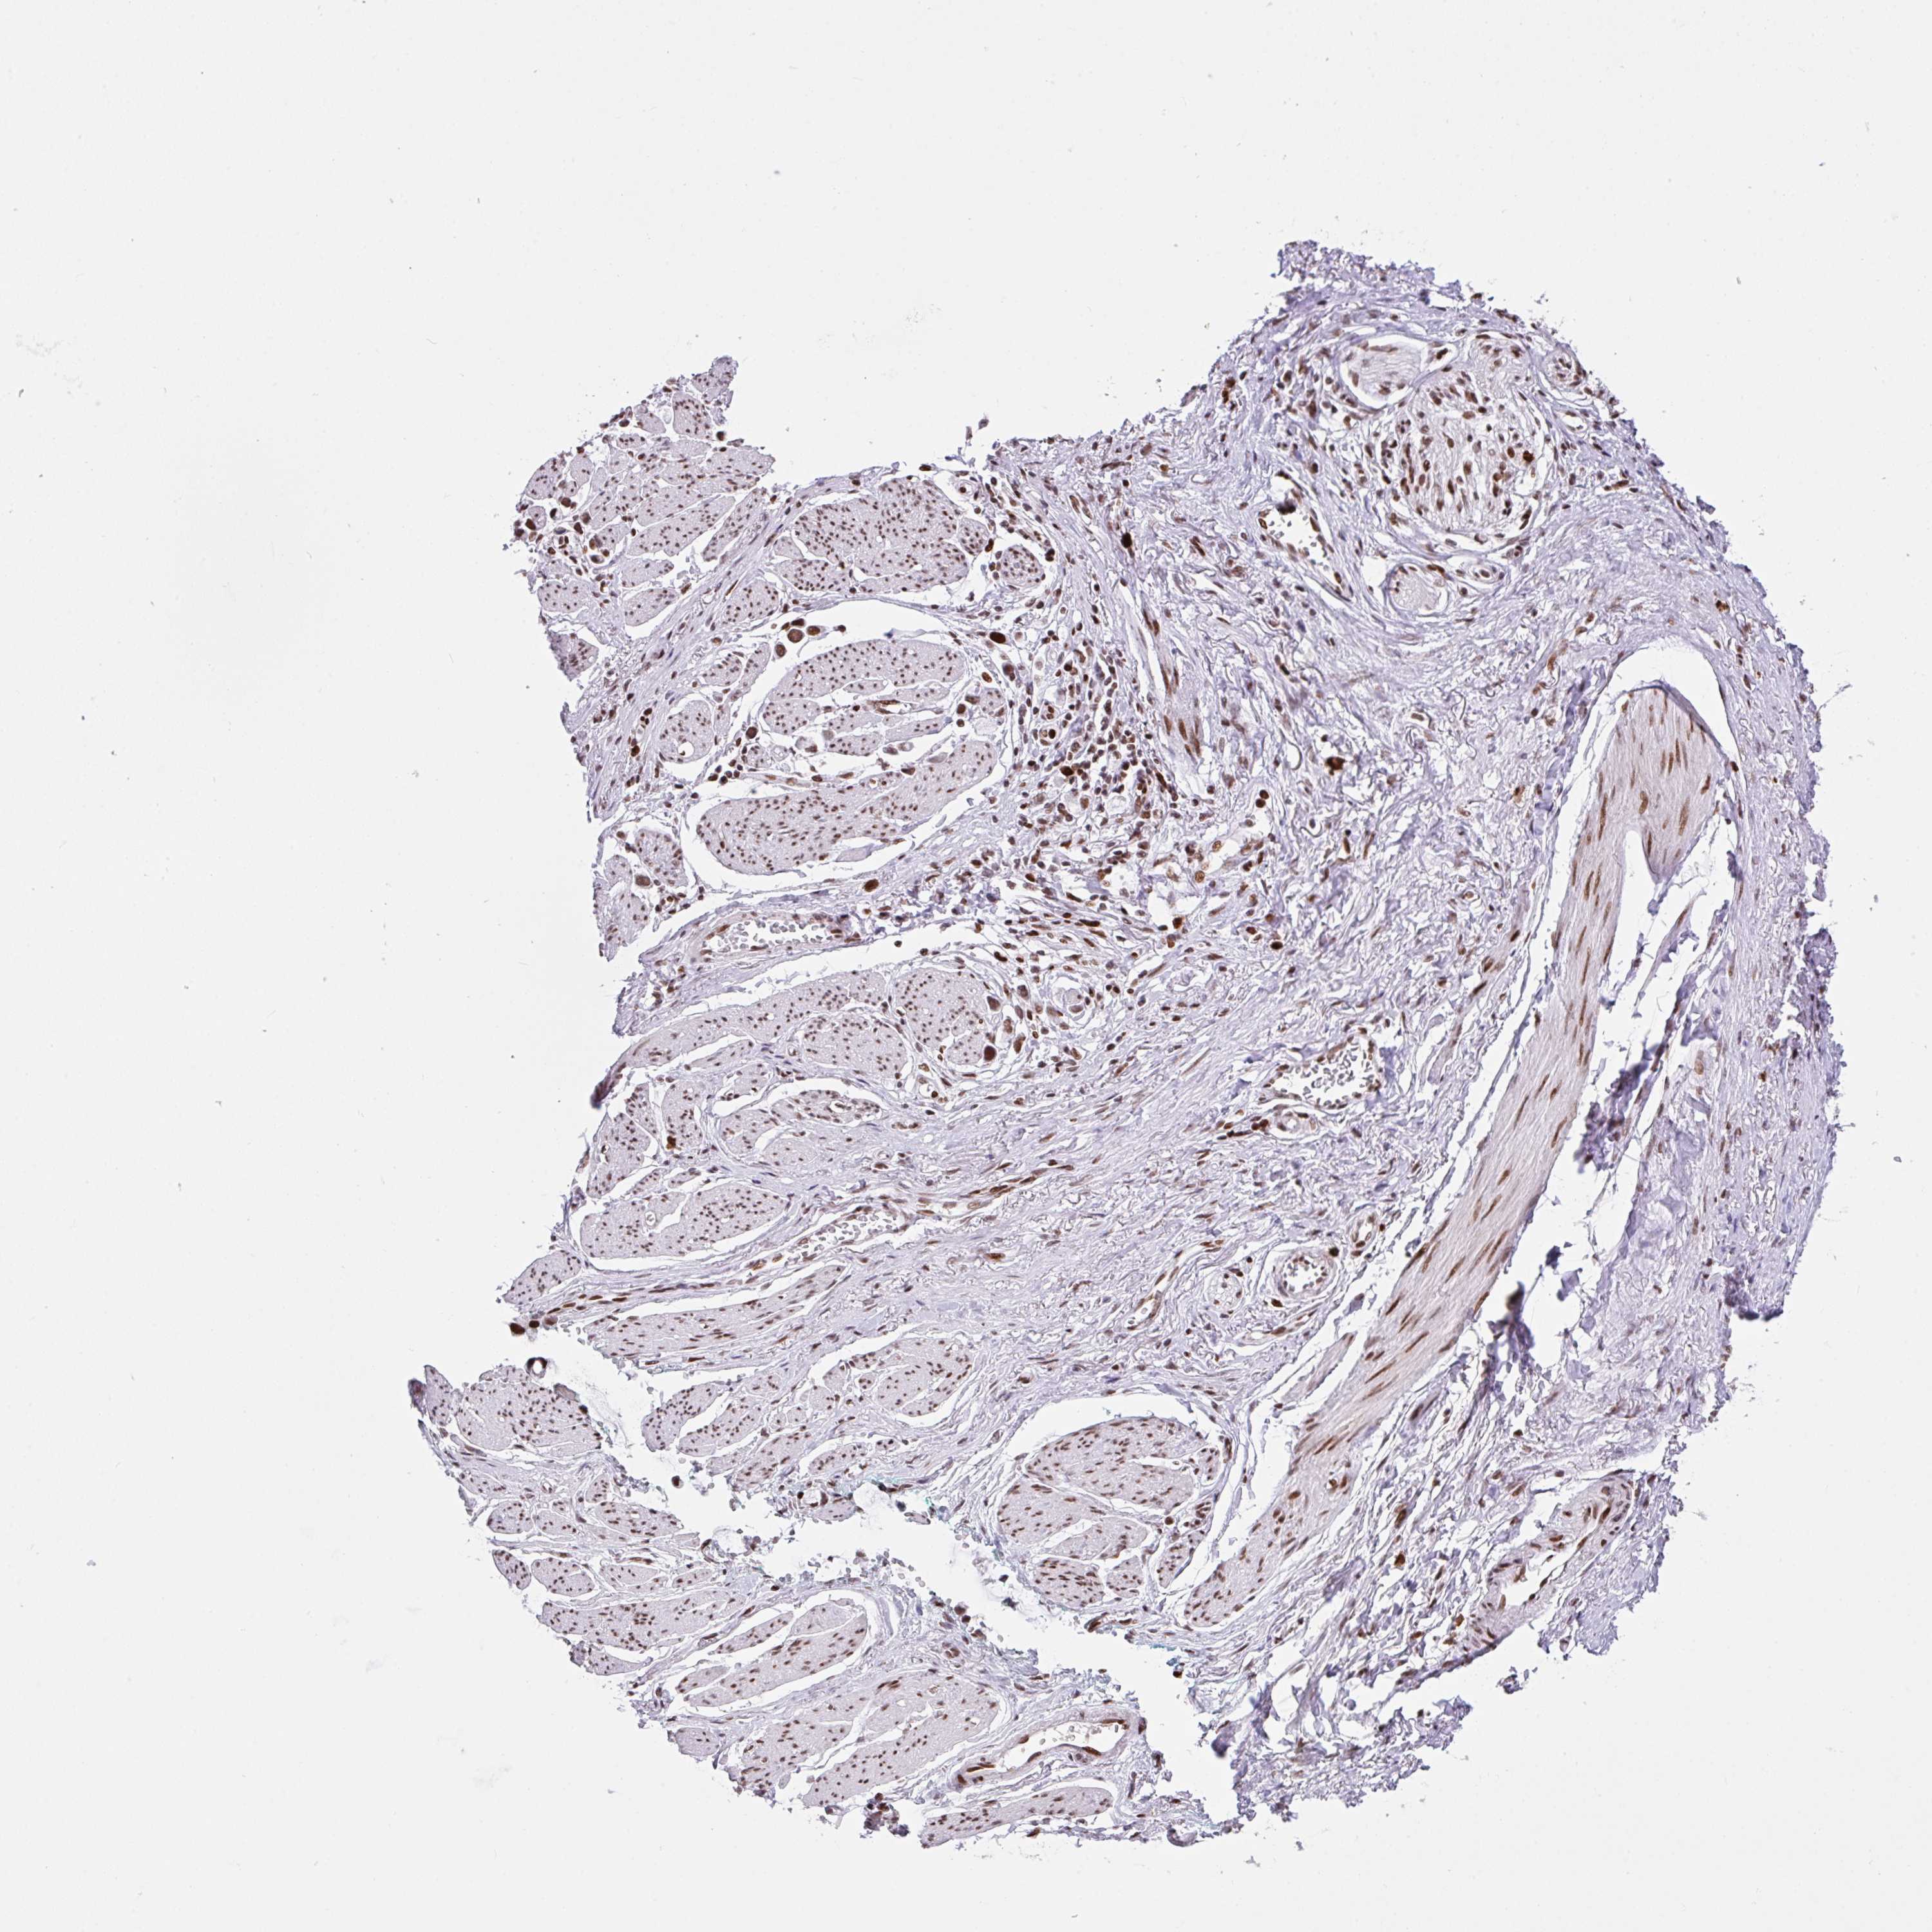

STOMACH CANCER - Protein expressioni

A mouse-over function shows sample information and annotation data. Click on an image to view it in a full screen mode. Samples can be filtered based on level of antibody staining by selecting one or several of the following categories: high, medium, low and not detected. The assay and annotation is described here.

Note that samples used for immunohistochemistry by the Human Protein Atlas do not correspond to samples in the TCGA dataset.

Antibody stainingi

Antibody staining in the annotated cell types in the current human tissue is reported as not detected, low, medium, or high, based on conventional immunohistochemistry profiling in selected tissues. This score is based on the combination of the staining intensity and fraction of stained cells.

Each image is clickable and will lead to virtual microscopy that enables deeper exploration of all samples and also displays staining intensity scores, fraction scores and subcellular localization as well as patient and tissue information for each sample.

Antibody HPA057770

Staining

High

Medium

Low

Not detected

Intensity

Strong

Moderate

Weak

Negative

Quantity

>75%

75%-25%

<25%

None

Location

Nuclear

Cytoplasmic/membranous

Cytoplasmic/membranous,nuclear

Adenocarcinoma, NOS